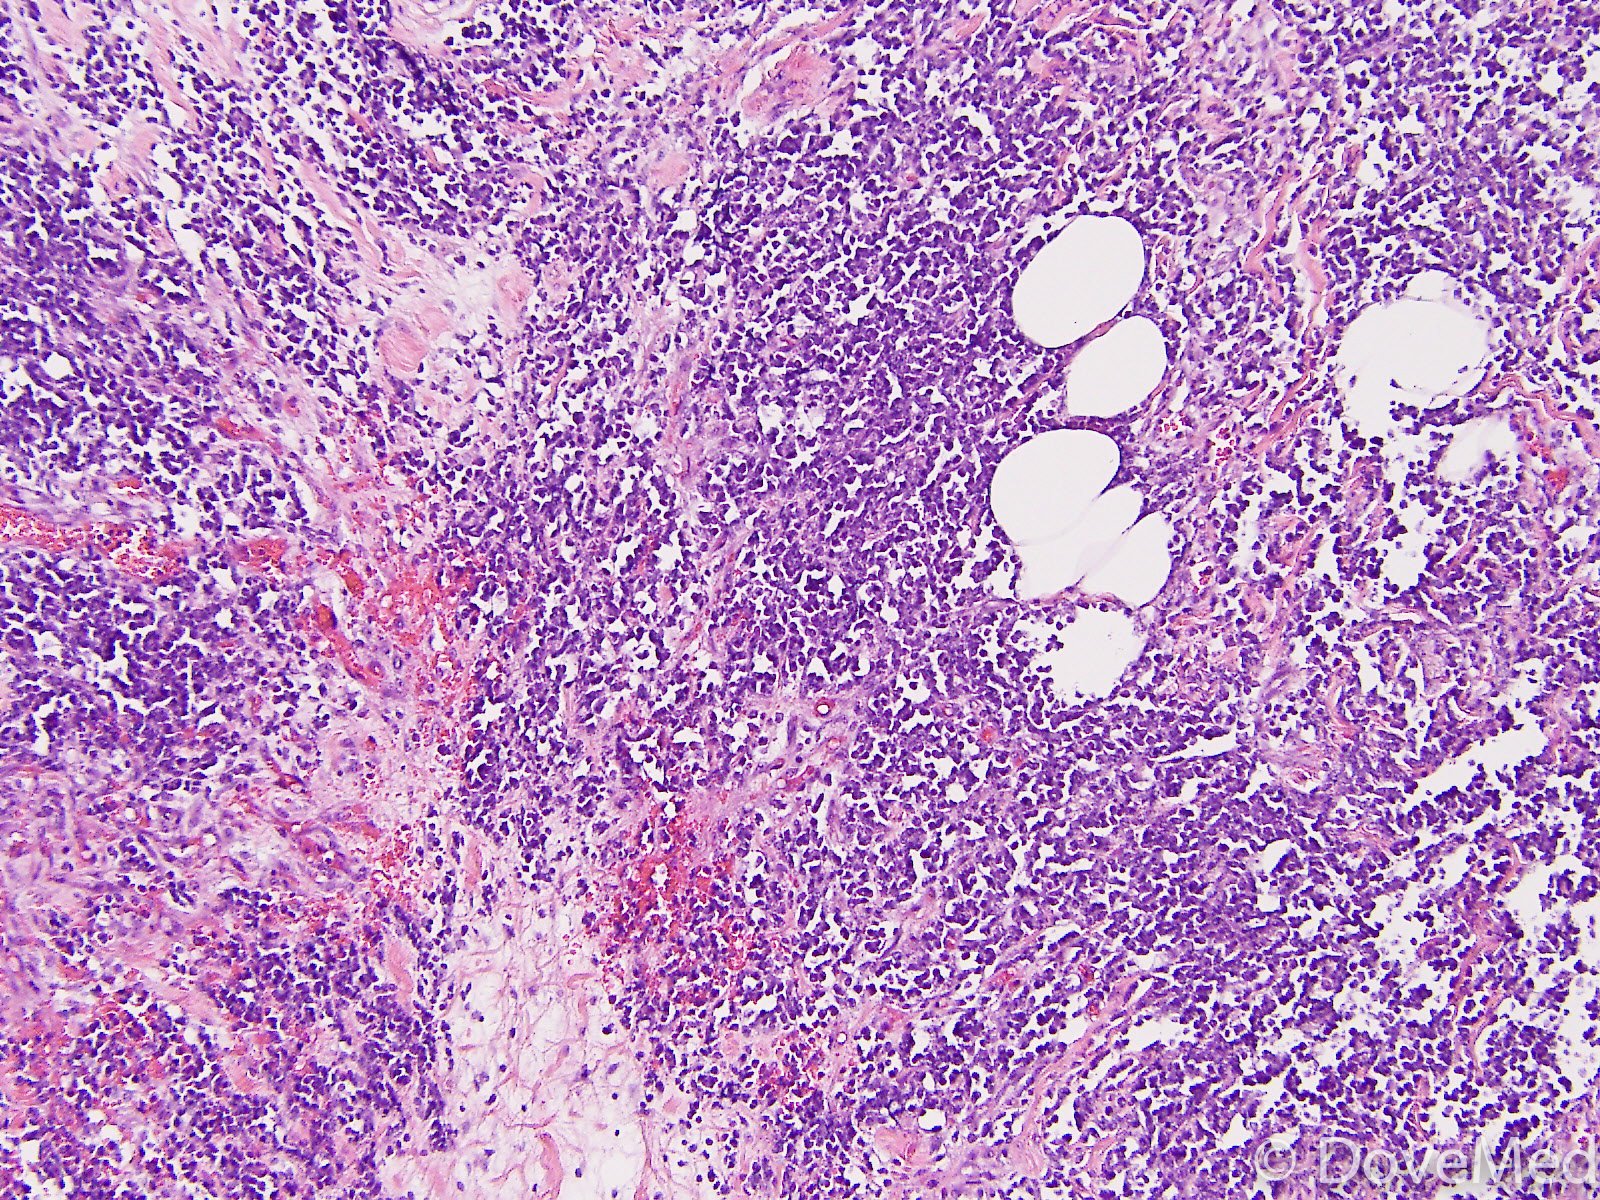

Das BL ist einer der am schnellsten wachsenden humanen Tumoren und hat entsprechend eine außerordentlich hohe Zellteilungsrate (der sogenannte Ki-67-Index ist größer 95 %, d. h. mehr als 95 % der Zellen befinden sich in Teilung). Gerade wegen des rasanten Wachstums ist der Tumor jedoch in der Regel sehr empfindlich gegenüber Chemotherapie und Strahlentherapie. Bei ausgeprägtem Knochenmarkbefall durch das BL (>20 % Zellanteil) spricht man auch von Burkitt-Leukämie oder „reifzelliger B-ALL“/„L3-ALL“. Dies ist ein seltenes Krankheitsbild (nur ca. 3–5 % aller akuten lymphatischen Leukämien, d. h. in ganz Deutschland weniger als 100 Fälle pro Jahr).